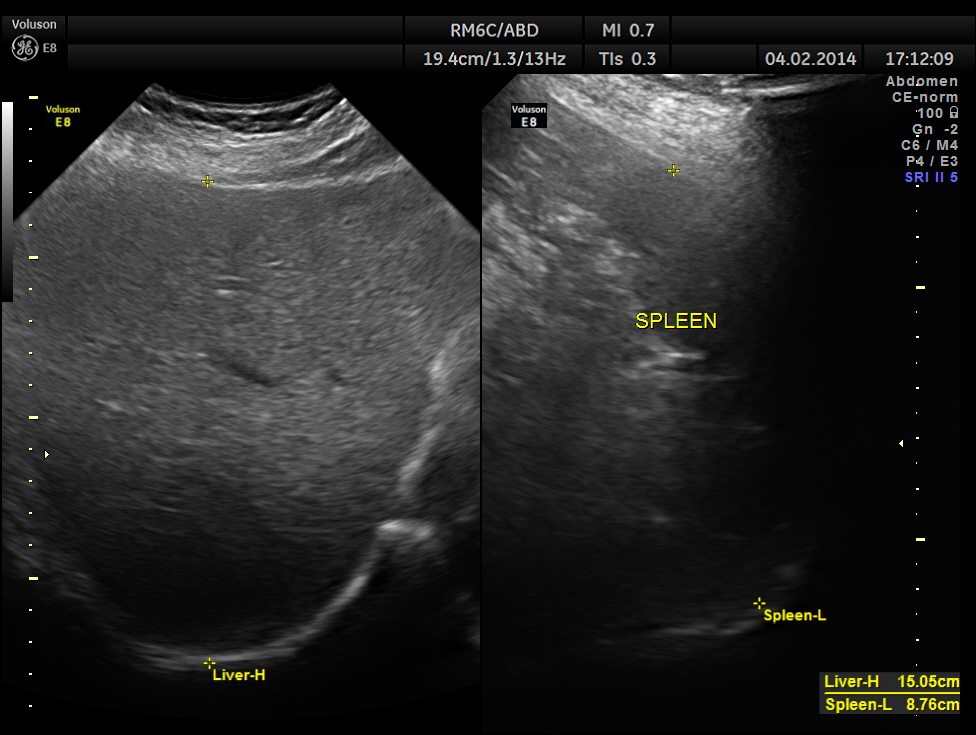

He came for a repeat scan 50 days later.

The C.B.D. measured 5.70 mms ( still within the normal range ).There was no evidence of any obstruction .

The pancreas appeared to be normal.